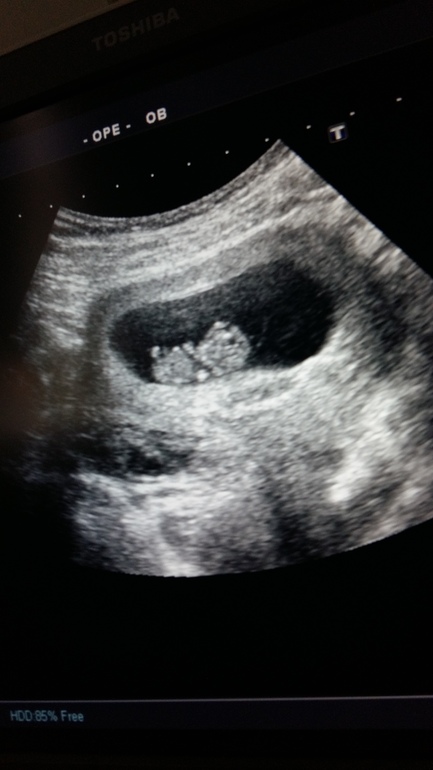

В общем по УЗИ все хорошо у нас. Угрозы нет. Все в норме. Срок поставила 9-10 нед. По мес. вчера было 10.4. По овуляции на недельку меньше-9.4.

И вот такие наши параметры:

Плодное яйцо-59мм.

Хорион кольцевидный по задней стенке, толщиной 9мм.

КТР-26ММ.

А такие стали))) разница 26 дней